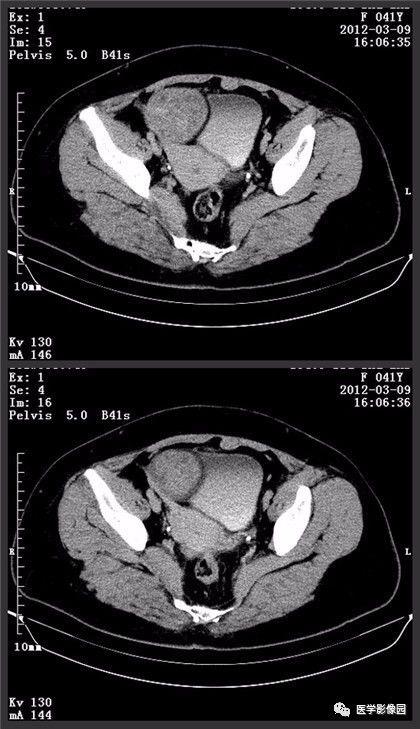

正常附件卵巢ct图片,女性盆腔ct解剖图

ct49785:女性,36岁.月经不调,检查发现左卵巢可疑包块